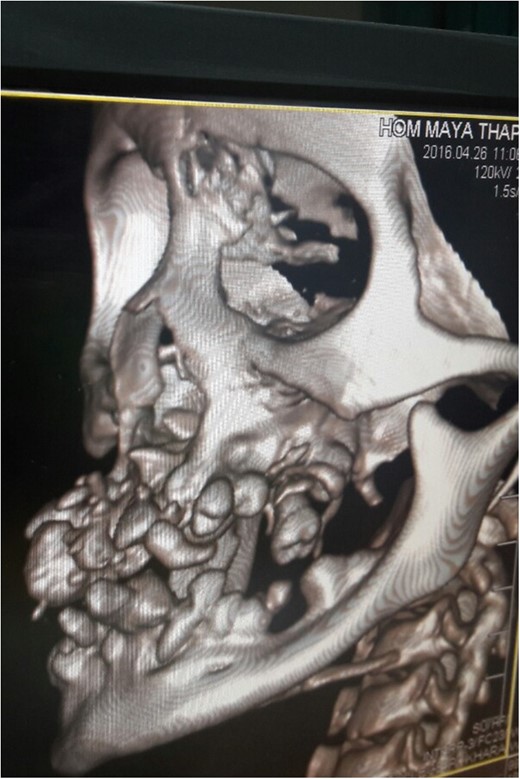

Her younger sister with age 17 years also presented 4 months later with similar complaints (Fig. 4). She also had normal deciduous teeth but did not have any permanent teeth eruption. She had difficulty in mastication and speech as well. She was mentally sound and did not have any other abnormalities. All her routine investigations were normal. X-ray (Fig. 5) and CT (Fig. 6) scan showed permanent teeth in both upper and lower arch which were malpositioned, unerupted and impacted in fibrous growth. Biopsy was taken from the gingival growth of younger sister which showed stratified squamous lining and subepithelial tissue showed collagenous fibrous connective tissue with mild chronic inflammatory cells (Fig. 7). Diagnosis of FGF was given. She underwent two stage gingivectomy 2 weeks after the initial diagnosis of FGF (Fig. 8). She is doing well and able to close her lips on post-operative follow-up (Fig. 9A). Later, prosthetic rehabilitation was done with upper and lower complete removable denture to the younger sister (Fig. 9B).

CT scan of younger sister showing permanent teeth in both upper and lower arch which are malpositioned and unerrupted and impacted.